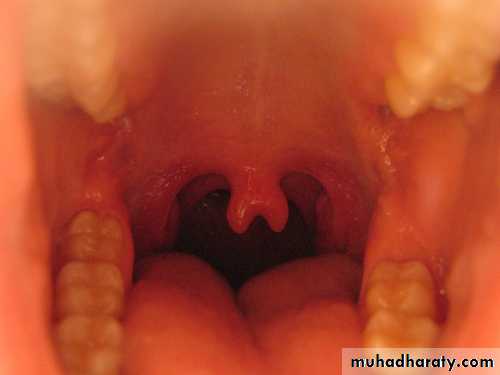

bifid uvula:normal or associated with a submucous cleft palate.

Bifid uvula